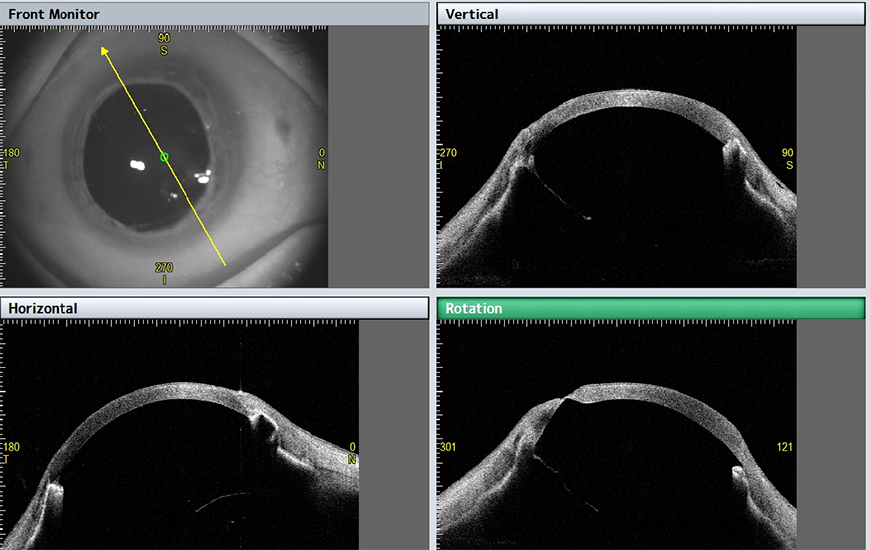

- Analiza kąta przesączania w 360°,

- zaawansowane obrazowanie ze zwiększoną głębią obrazowania (13mm) i prędkością skanowania (50.000 A-scan/sek),

W aplikacji STAR 360°, CASIA2, dzięki automatycznemu wykrywaniu ostrogi twardówki mierzy kąt przesaczania na pełnym obwodzie przedniego segmentu, co zapewnia szczegółowe parametry umożliwiające perfekcyjną diagnostykę jaskry.

Nie tylko mierzy, ale także wyświetla wynik na szczegółowym wykresie/mapie graficznej. Wykresy można wybierać spośród wszystkich wartości pomiarowych w zależności od własnych potrzeb.